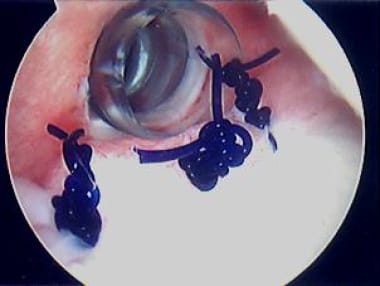

An arthroscopic interval closure is also typically added to reduce inferior laxity; this may be done last, after completion of plication sutures (see the images below).

View from posterior portal of "interval closure"; with suture passer device, monofilament suture is placed at margins of cuff interval. Photo courtesy of Daniel C Wnorowski, MD.

Knot is tied through anterosuperior portal, thus closing rotator-cuff interval. Photo courtesy of Daniel C Wnorowski, MD.